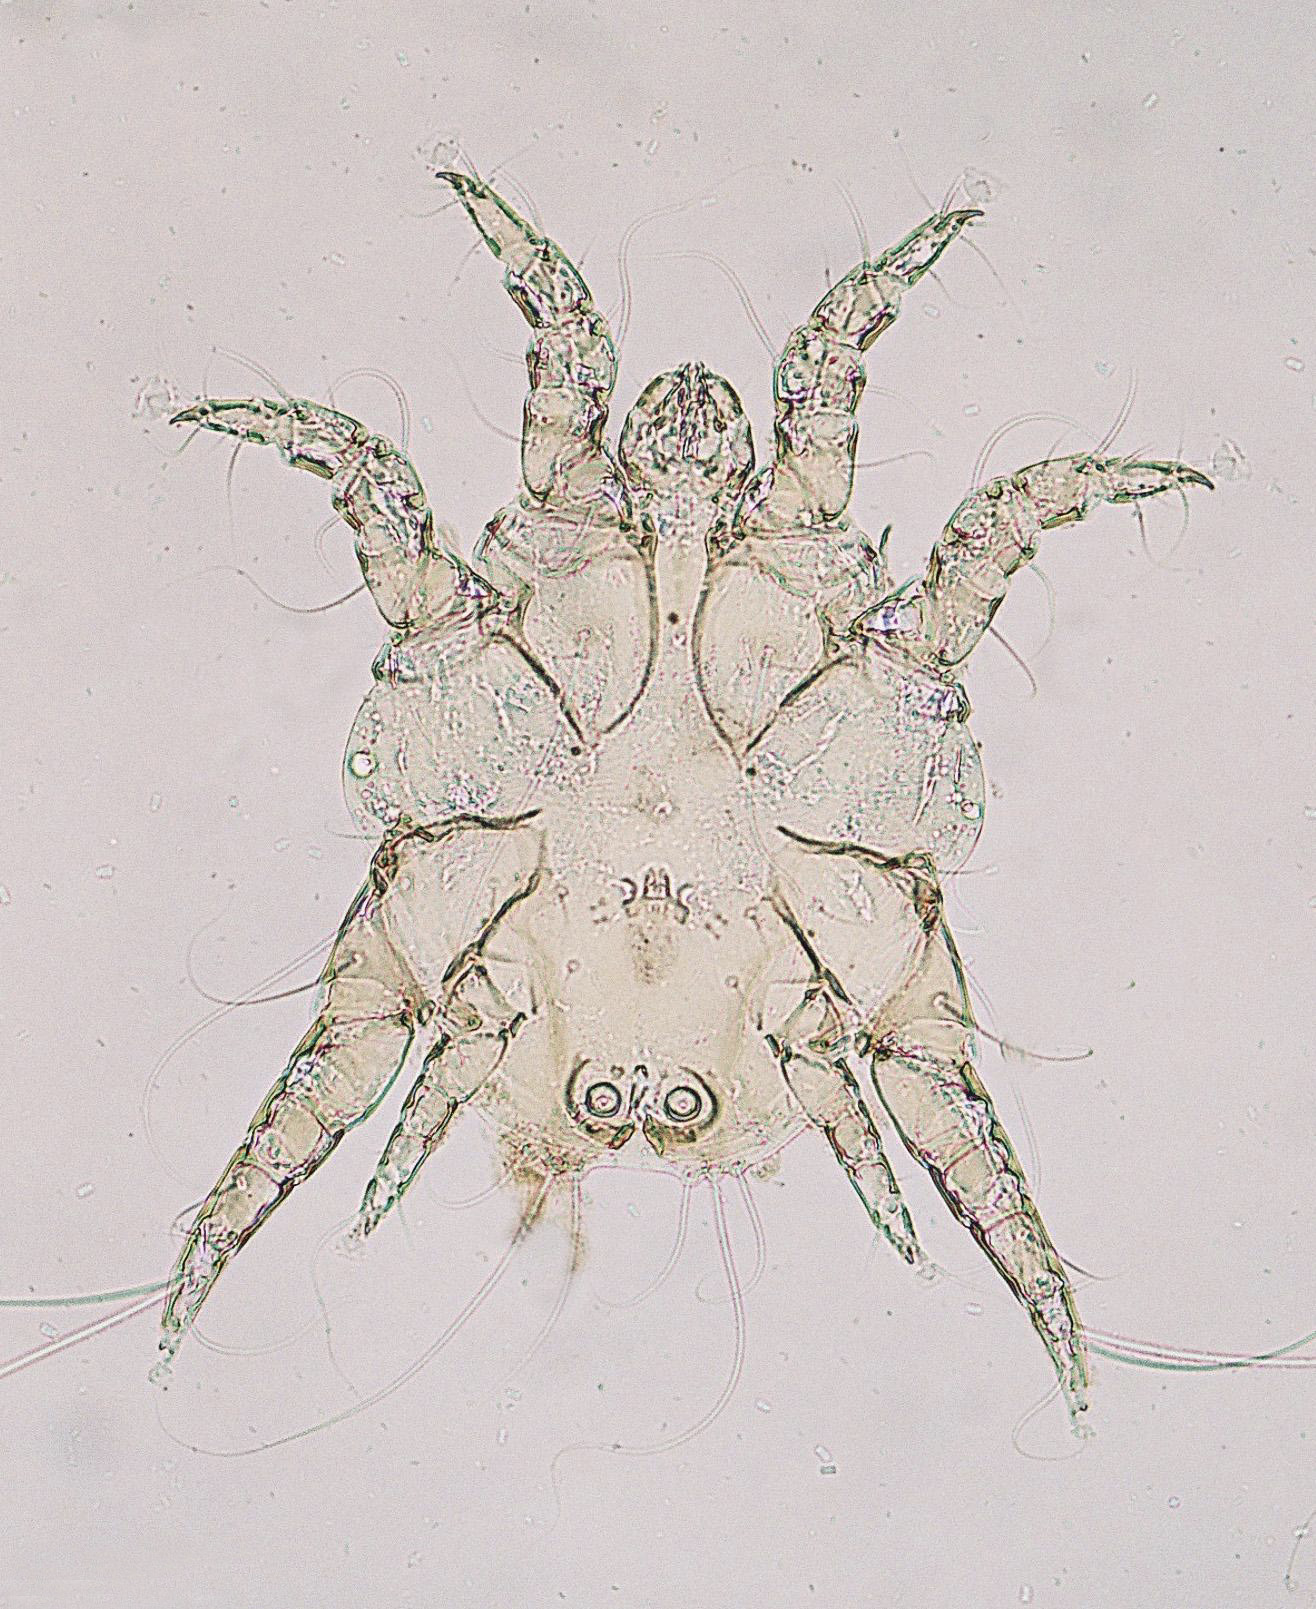

Demodex canis/cati/equi

demodex